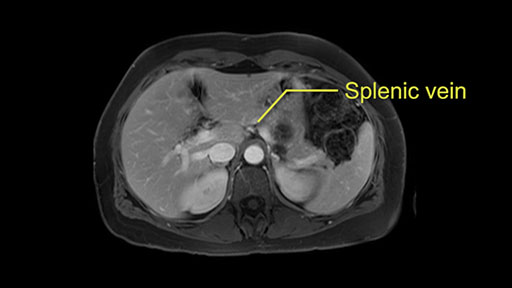

Other slowing down moments with this procedure include dissection of the splenic vein and splenic artery. These are technically challenging moments and important moments where care needs to be taken. Not only to avoid bleeding and injury to the vessels but also to ensure an adequate margin.

The second slowing down moment or consideration I give to a distal pancreatectomy is the anatomy of the portal vein and the splenic artery. And so I look here and the anatomy is pretty straightforward. The splenic vein comes off normally and runs behind the pancreas and I can see the artery superior to that, again coming off in a normal manner from the celiac axis. So those two things, the portal vein and the splenic artery will be taken normally in this procedure.